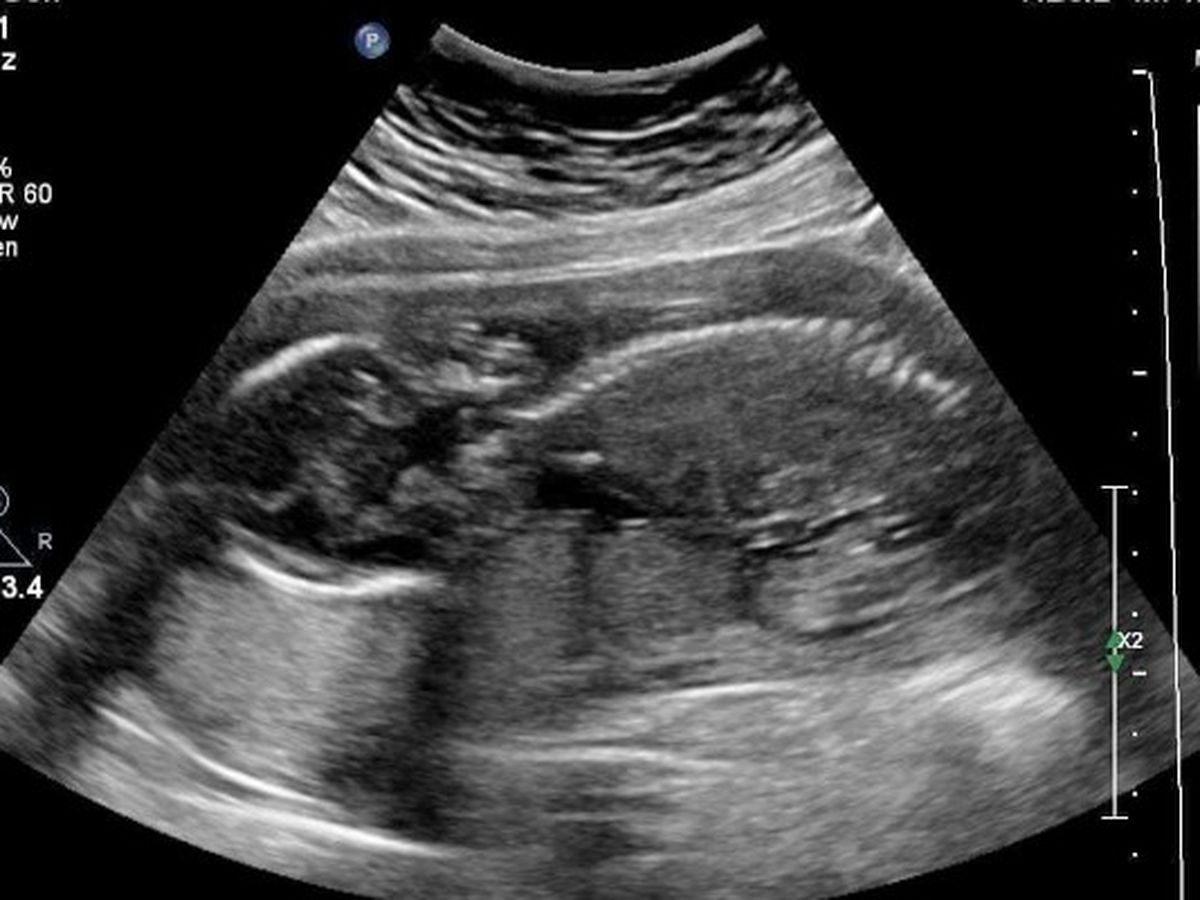

On our 24 week ultrasound we found out our baby may have a birth defect called gastroschisis which is a condition where the intestines were growing through a hole outside of the body. It is currently unknown why it occurs. There is a 95% survival rate. Our doctor sent us to edmonton for a more advance ultrasound and thats when they confirmed the gastroschisis and will need surgery unfortunately grande prairie doesnt have the right doctors / nicu so we will have to relocate to edmonton at 35 weeks pregnant and will need to stay there until baby is stable enough to come home which we could be there 1 month and a half or even longer, depending on how much organs are out and inflamed, and how the surgery and healing goes .